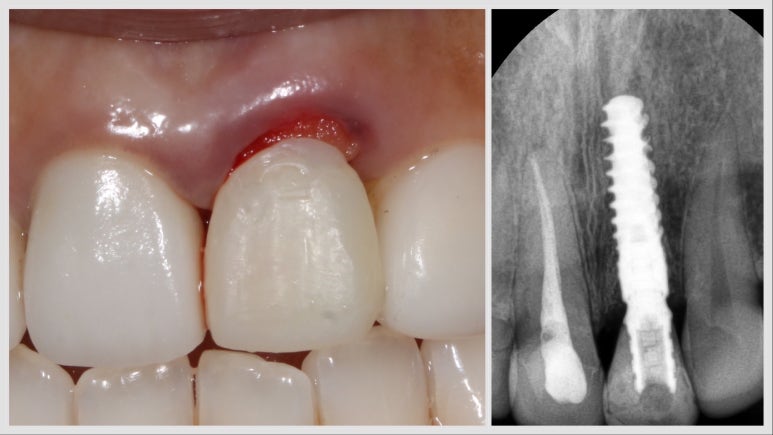

수술 전 상황 - 치근 파절 #21번 치아

이 환자분의 경우 왼쪽 앞니 (사진상 오른쪽) 치아가 뿌리 쪽이 부러져서 내원하신 경우인데요. 위와 같이 뿌리 중간이 부러진 경우 더 이상 치아를 살리기 어려워서 발치 후 임플란트를 하게 된답니다.

정면에서 일단 저한테 가장 중요하게 신경 쓰이는 부분은 잇몸 높이가 달라서 치아 크기가 비대칭이라는 부분인데요. 아래 사진에서 볼 수 있듯이 치아가 부러진 후에 앞쪽으로 많이 이동되어 잇몸이 올라갔다고도 볼 수 있을 것 같습니다.

수술 전 - 임플란트 수술 후 - 임시치아 장착 후 엑스레이 사진

이런 경우 임플란트 수술에 있어서 1차 원칙, 가능한 한 최소침습적인 방식으로 발치를 하고, 당일 바로 임플란트 나사를 식립한답니다. 이 환자분의 경우 발치 후 즉시 식립 시 초기 고정을 얻기 쉬운 #스트라우만 BLX 임플란트를 사용하여 수술을 진행하였답니다.

수술 직후 당일 사진 및 엑스레이

수술 직후의 사진인데요, 위 환자분의 경우 플랩리스 방식, 비절개 방식으로 발치를 하고, 임플란트 나사를 심은 후, 주변에 뼈이식을 한 후에, 임플란트에 임시치아를 직접 연결하여 제작하고, 잇몸 높이가 최대한 대칭이 맞게 끔 임시치아 모양을 조정했답니다. 플랩리스 방식으로 봉합을 하지 않고 수술을 마무리했답니다.

한번 수술에, 제가 원하는 모든 것을 한 셈이지요.